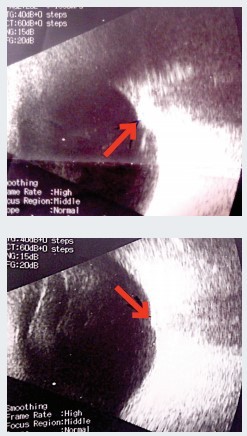

Рисунок 1. Эхоскопия. Стрелка указывает на ДЗН, проминирующий в стекловидное телоЭхоскопия. ОD — умеренная деструкция стекловидного тела, задняя гиалоидная мембрана (ЗГМ) частично отслоена, оболочки прилежат, в ДЗН гиперэхогенное включение (друзы?). OS — умеренная деструкция стекловидного тела, ЗГМ частично отслоена, оболочки прилежат, в ДЗН гиперэхогенное включение, ДЗН проминирует в стекловидное тело (см. рис. 1).

Осмотр глазного дна с фундус-линзой. OS — в основании ДЗН округлое проминирующее пигментированное (меланоцитома?) образование, границы и ткань ДЗН не определяются, мелкая капиллярная сеть по поверхности ДЗН, гиперпапиллярно отек нейроэпителия сетчатки (НЭС). Окклюзия артерий по верхневисочной и носовой аркадам, в зоне верхневисочной и верхненосовой аркад молочно-белый отек сетчатки с захватом верхней части фовеа. Сетчатка прилежит (см. рис. 2). Лазерная коагуляция не показана. Рекомендована консультация онкоофтальмолога.